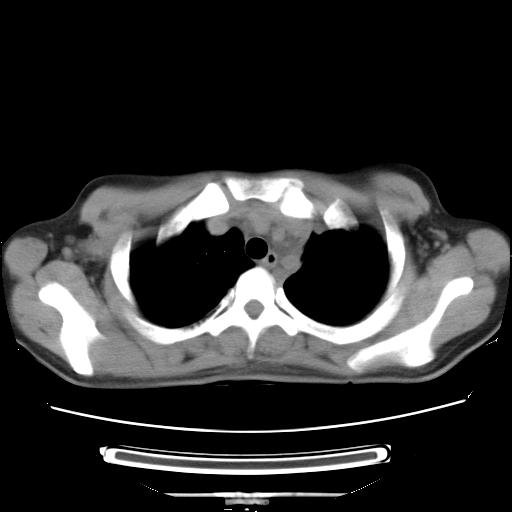

标题: CT21561:外院胸片提示胸腔积液,行CT检查。 [打印本页]

女,29岁,胸部不适,在外院胸片提示胸腔积液,到我院ct检查。

纵膈窗